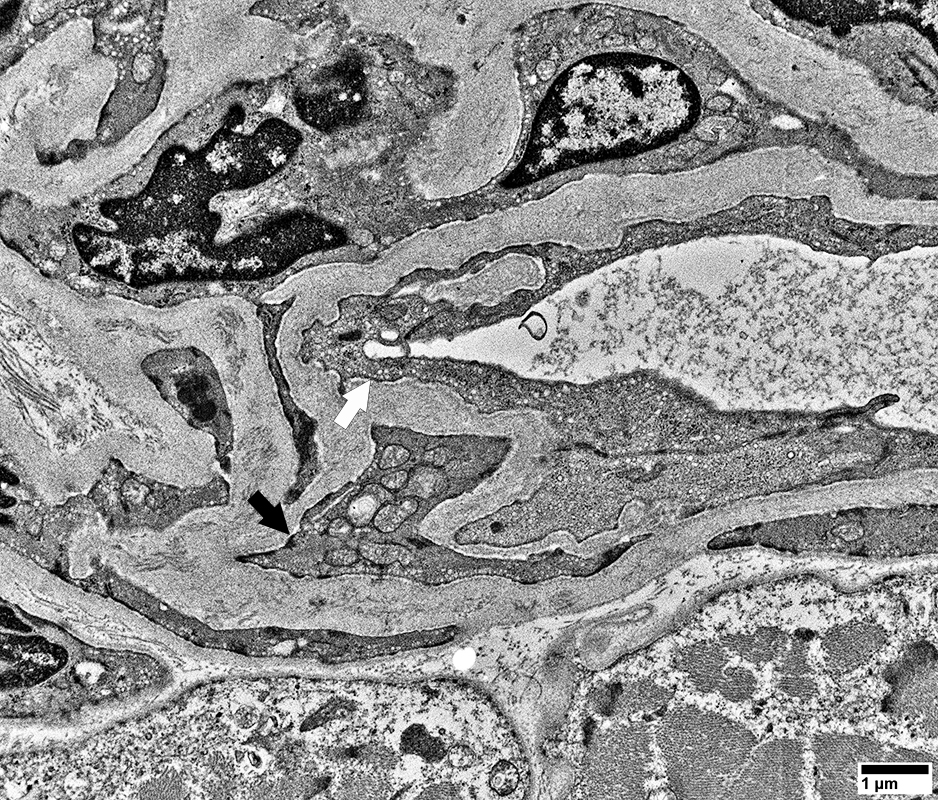

Endomysial vessels with

Large endothelial cells with many vesicles

No lumen

Many smooth muscle cells in wall, some with mitochondrial proliferation (Arrow)

Thick wall

From: R Schmidt